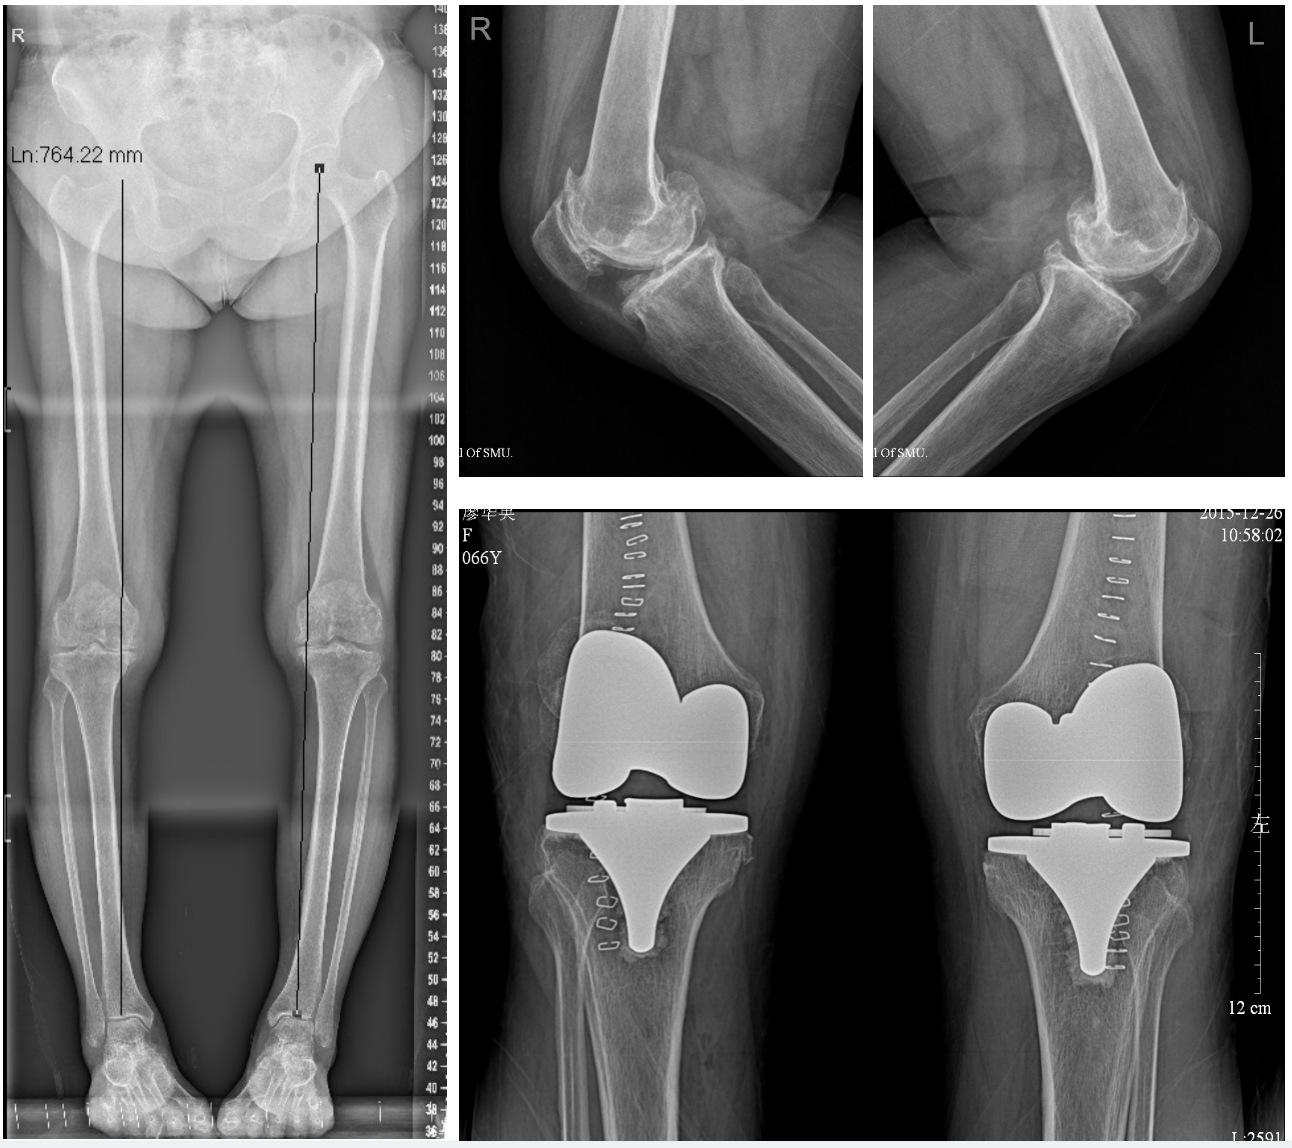

全膝关节置换术的术前和术后X片,手术范围涉及膝关节三个间室

膝关节置换手术是利用人工膝关节假体置换系统,治疗膝骨性关节炎、类风湿性关节炎等膝关节终末期疾病的一种主要手术方式,能有效矫正畸形、解除症状、恢复膝关节功能,提高患者生活质量。

根据解剖特点,膝关节按空间可分为内侧间室、外侧间室、髌股关节间室和髁间窝。膝关节置换手术的范围包括股骨远端和胫骨远端相对应的关节面(双间室置换术),部分还包括髌股关节面(三间室置换术)。但如果患者的膝关节退化仅涉及膝关节内侧单间室,这时候就可以考虑行微创膝关节单髁置换术(单间室置换术)了。但是单间室置换术适应症较局限,手术前必须经过详细的检查才能确定患者是否符合手术指征,而非每个膝关节骨性关节炎的患者都适合手术。下面我们来看一下究竟有哪些条件: